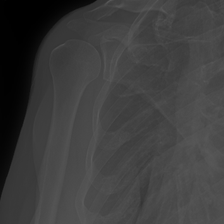

MURA Musculoskeletal Radiograph Dataset – Obtained from 14,863 bone X-ray studies, Stanford’s MURA dataset involves the identification of abnormalities such as bone fractures and hardware implants [21].

Using the trained models with state-of-the-art performance, we follow the protocol detailed in Section 2.4 and present experimental results on interpretability in Figure 3, Figure 4, and Table 3. In particular, Figure 3 illustrates several qualitative examples, while Table 3 displays pointing game accuracy and mean IoU scores. Finally, Figure 4 represents IoU distributions represented in the form of boxplots. Based on these results, we make the observations below.

Qualitative results can be misleading. In Figure 3, we present qualitative interpretability outputs for all methods considered. As can be seen, depending on the selected subset of images and the method, both accurate and inaccurate interpretability maps can be found. These findings emphasize the danger of making strong claims about interpretability methods based solely on qualitative results, including attention maps.

Bounding box annotations may be inadequate for interpretability evaluation on medical datasets. In this work, we worked with expert clinicians to highlight disease-positive regions with a bounding box to evaluate the efficacy of interpretability maps. However, we discover that this approach comes with significant shortcomings. For instance, in the MURA and Kvasir datasets, regions of interest often occupy large spaces, resulting in annotation boxes that include non-target areas, and leading to inflated results regardless of the method’s actual precision. Therefore, using segmentation maps, which provide detailed pixel-level annotations of the areas of interest, could offer a more precise evaluation in future research.